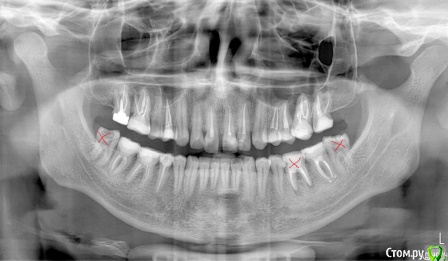

Собираюсь надеть брекеты, на консультации ортодонт сказала, что нужно удалять верхние 4ки и один нижний зуб справа (слева 6ки у меня нет). Действительно ли это необходимо? Просто все чаще натыкаюсь на случаи, когда люди потом обратно раздвигают зубы и ставят импланты. Вот КЛКТ 16x16 - https://yadi.sk/d/40q5jLjb3JUzLN

ТРГ нет, только КТ. Хотелось бы понять, оправдано ли удаление верхних четверок. + ко всему корни их вроде как выступают в пазуху, это тоже лишние осложнения. Был у 3х ортодонтов, один как увидел КТ предположил, что скорее всего нужно будет удалять, другой сказал что ничего не надо, что перетянем все назад и так, третий сказал что пограничный случай, в ходе лечения разберемся (правда смотрел он только панорамный снимок). Мнения очень полярные

по предоставленным данным сказать сложно, но попробуйте посетить консультацию ортодонта, владеющего многопетлевой дугой, с ее помощью в большинстве случаев удается провести коррекцию похожих ситуаций без удаления премоляров, 6-ой зуб я бы удалять не стала.